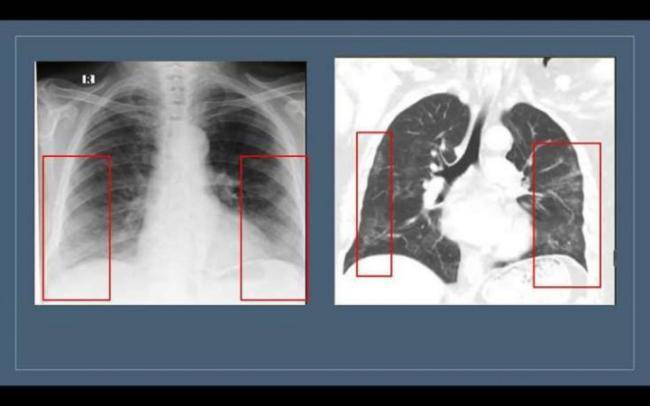

“Buzlu şüşə” görüntüsü döş qəfəsinin rentgenoqrafiya və KT müayinələrində aşkar edilir. Lakin bu məsələdə rentgenoqrafiya müayinəsinin həssaslığı aşağıdır. Ona görə də yoluxmanın ilk 1-4 günlərində rentgenoqram 25% hallarda tam normal ola bilər. Bu, pnevmoniyanın olmaması demək deyil. “Buzlu şüşə”nin KT müayinəsində görülməsi daha spesifikdir", həkim bildirib.

Bu o deməkdir ki, normalda şəffaf havalı görünən ağciyərdə belə hallarda yarımşəffaf zonalar izlənilir, ağciyər sanki dumanlı görünür. Bu zaman bronx strukturlarının və pulmonar damarların saxlanması ilə ağciyərlərin eksudat və ya transudatla tutulması, interstisial qalınlaşmalar və ağciyər alveollarının hissəvi kollapsı ilə müşahidə olunan görüntü meydana çıxır. Buzlu şüşə xəstəliyin 3-4 günlərindən inkişaf etməyə başlayır və xəstə sağaldıqdan hətta bir ay sonra belə qala bilir. Xəstəliyin yüngül və orta ağır dərəcəsini keçirmiş xəstələrdə 2-3 aydan sonra dəyişikliklər tamamilə itir”.